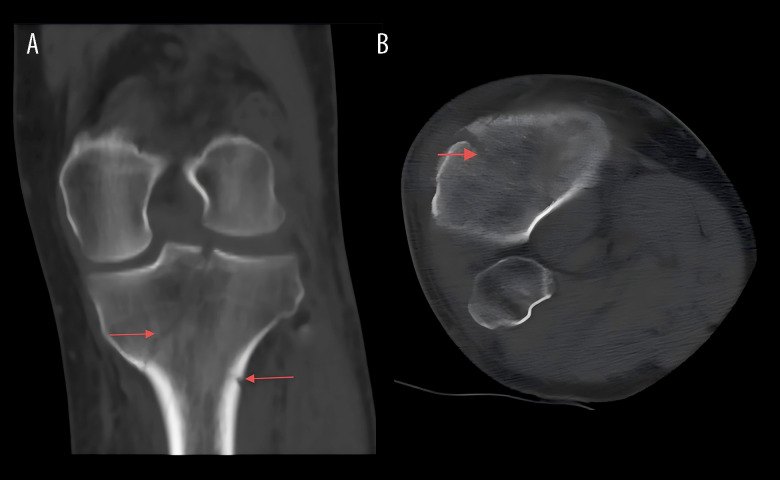

BACKGROUND Conventional clinical understanding holds that venous thrombus formation typically occurs days after traumatic injury. However, our findings demonstrate that acute thrombosis can begin within 7.5 hours after fracture in knee trauma cases, challenging existing paradigms. CASE REPORT A 43-year-old man was admitted to the Emergency Department (ED) after an electric bicycle accident precipitated by acute-onset dizziness accompanied by visual disturbances. Initial radiographic evaluation confirmed a comminuted right proximal tibia fracture with concomitant multiple acute ischemic cerebral infarctions on neuroimaging. Compression ultrasonography performed in the ED showed no evidence of deep venous thrombosis in the lower extremities. However, markedly elevated D-dimer levels (9.39 mg/L; reference <0.5 mg/L) prompted high clinical suspicion for occult venous thromboembolism. Serial Doppler ultrasound surveillance revealed the rapid development of a free-floating thrombus in the right soleal vein within 7.5 hours after the fracture occurred. CONCLUSIONS This case report documents the exceptionally rapid development of venous thrombosis within 7.5 hours following a proximal tibia fracture, particularly in high-risk patients with comorbid conditions such as diabetes mellitus and ischemic stroke. These findings necessitate immediate reassessment of current thromboprophylaxis protocols in orthopedic trauma, emphasizing the critical importance of early and frequent vascular monitoring (including serial Doppler ultrasonography and D-dimer assessment) to detect hyperacute thrombus formation. Clinicians must maintain heightened awareness of this emergency thromboembolic risk while simultaneously managing hemorrhage concerns, as this case demonstrates that the traditional 24-hour prophylaxis window may be inadequate for certain high-risk trauma populations.